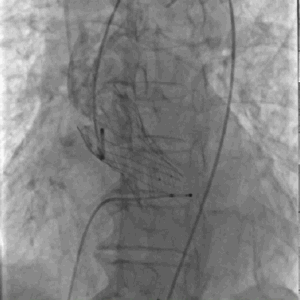

瓣膜定位

快速释放瓣膜

瓣膜到位,患者突然心跳骤停,立即给予胸外心脏按压并快速释放瓣膜,之后继续胸外心脏按压,肾上腺素静推。

瓣膜完全释放,形态良好、无周漏

经过以上处理,患者心跳恢复、血压回升、术后压力阶差降至小于3-5mmHg,瓣膜形态良好,极少量瓣周漏,但患者随后出现持续性室性心动过速。